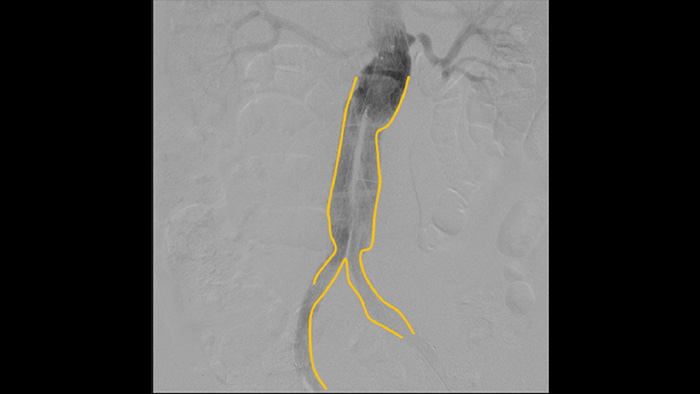

アウトラインツールを使用することでモバイルビューイングステーションのモニター上に指またはマウスを使用してモニター上に滑らかな線を描くことができます。血管の分岐または側枝に簡単にマーキングすることが可能です。